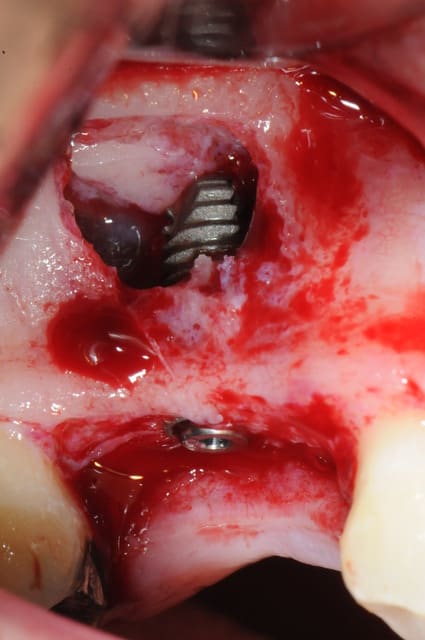

je sais pas si c'est un produit miracle, mais pour les sinus lift, c'est fantastique.

outre le fait de stabiliser un implant dans un sinus type SA4, pas de risque de voir partir le produit comme avec les granules de bioos et autres..

l'autre avantage est de ne pas avoir à mettre de membrane de recouvrement.

je suis donc hyper satisfait du résultat.

jugez plutôt...

l'application type du VitalOs, avec le bone splitting.

le protocole tel qu'il est d'écrit voudrait que l'on applique d'abord une couche de vital os en palatin - laisser durcir - mettre l'implant puis mettre une dernière couche.

ici, j'ai mis l'implant- maintenu la membrane de Schneider en poussant avec l'embout sur celle ci et terminer l'injection du produit. c'est l'un des avantages de ce produit, il est livré avec deux embouts donc les deux solutions sont possibles pour une même seringue.